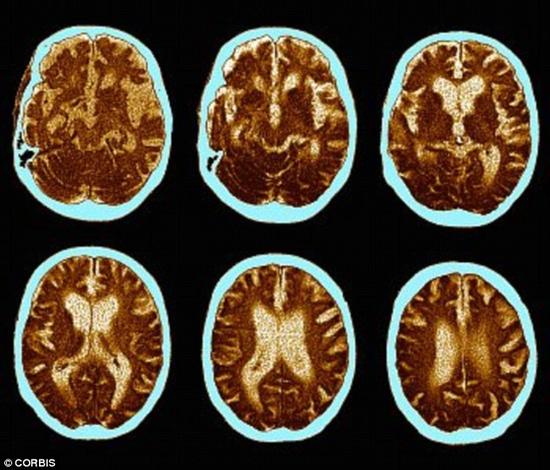

性生活频繁的老人出现痴呆的可能性更低。一项研究指出,规律的性爱活动能够帮助我们长出新的脑细胞。图为痴呆病人的脑部扫描。

延缓痴呆 我们的大脑会随着衰老而变得迟缓,很多人都清楚这一点。事实上,到35岁的时候,我们每天会损失多达7000个脑细胞,这会降低我们的阅读能力。 不过,据美国普林斯顿大学的科学家称,规律的性爱活动能够帮助我们长出新的脑细胞。并且,你享受的性爱越多,长出的脑细胞似乎也就越多。在动物身上进行的研究结果显示,性交会促进脑部海马体中的脑细胞生长,而这一部分掌管了我们的记忆和学习能力。压力、沮丧等因素会使海马体萎缩,而运动、性交的效果则刚好相反。 此外,性交的确能保护我们的脑细胞,防止功能衰退。“有证据显示,性生活频繁的老人出现痴呆的可能性更低,可能有多种原因导致这一现象。”戈什医生说道。性爱会使更多血液流向大脑,因此提高了大脑中的氧气含量。 “核磁共振扫描显示,高潮时,大脑中的神经元比平时更加活跃,需氧量也更多。”罗格斯大学的心理学教授、性和神经科学领域的顶尖专家巴利·科米萨卢克(Barry Komisaruk)说道。 “神经元越活跃,它们从血液中提取的氧气也就越多。因此,更多含氧量丰富的血液将被输送至这一区域,带来更多的养料供应。” 戈什医生指出,就像促进脑细胞生长一样,性爱也能使女性的头脑变得更加灵敏。这是因为性爱过程中大量分泌的一些性激素——尤其是睾酮——能够提高专注程度、缩短反应时间。